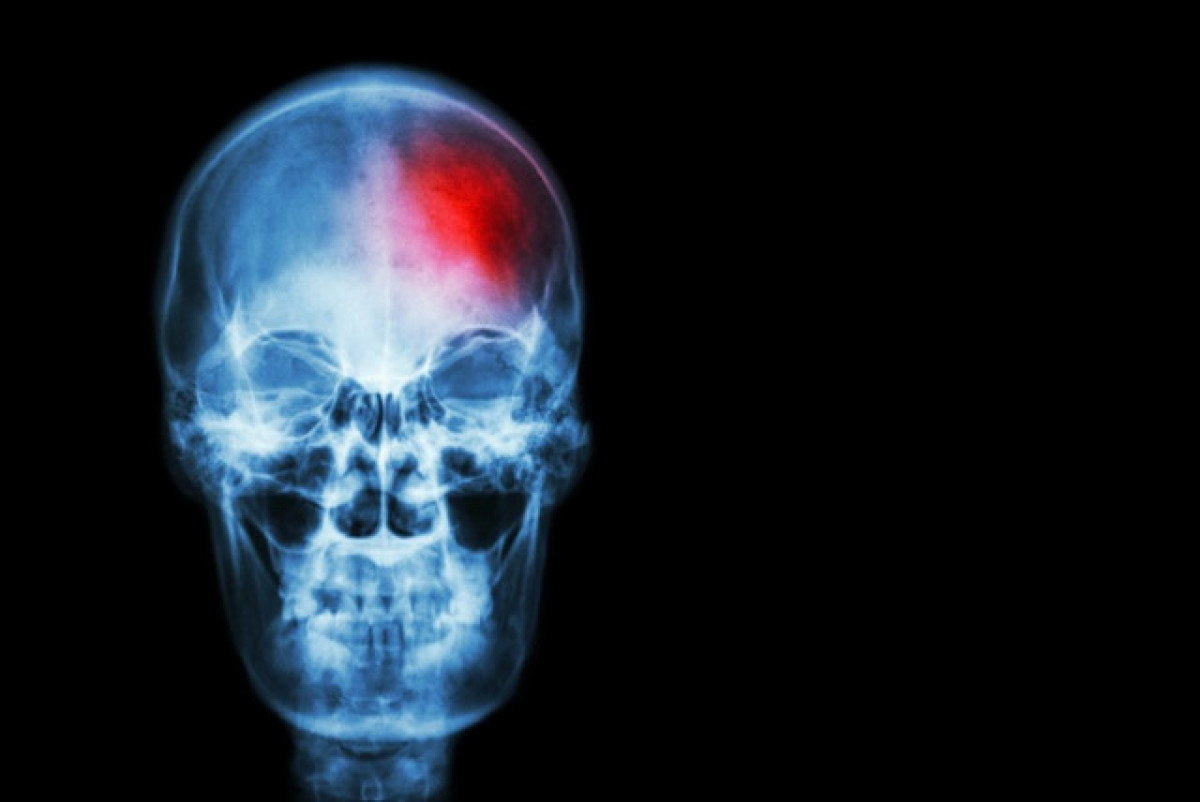

Un ictus /@EP

El neuròleg ens va explicar que hi ha dos tipus: “l'isquèmic i l'hemorràgic”. L' ictus isquèmic és el majoritari, es dóna en el 80 o 90% dels casos i succeeix quan una artèria es tapona per un trombe o qualsevol altra causa, la sang no pot passar i la part del cervell a què no li arriba es queda amb les funcions alterades. L'ictus hemorràgic succeeix quan un got cerebral es trenca i la sang entra al cervell. Tot i que dóna els mateixos símptomes, es pot veure que el mecanisme és diferent”, apuntava el doctor.